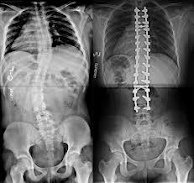

En esta ocasión explicaré sobre la escoliosis (desviación lateral anormal de la columna vertebral), puede ser en forma de "C" o de "S", como lo muestra la siguiente imagen:

Puede detectarse mediante una radiografía panorámica de columna, test de farill -para medir los miembros inferiores-, (ver imagen 1), una resonancia magnética, o una valoración fisioterapéutica: el profesional observará la postura y realizará una prueba (Adams), que consiste en colocarse de pie y luego agacharse como intentando tocarse la punta de los pies, dejando los brazos relajados o sueltos, para ver si un lado de la caja torácica es más prominente que el otro; o si la columna vertebral se desvía como se aprecia en la imagen 2.